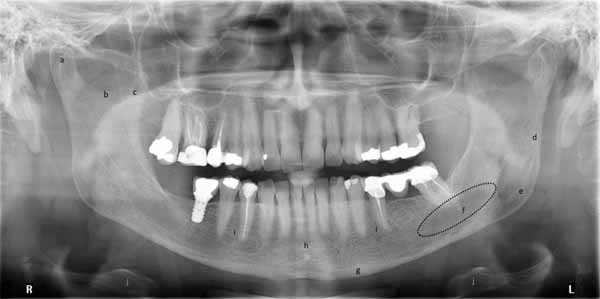

パノラマX線画像における硬組織構造

まず、硬組織構造を調べます。わかりやすくするために、これらすべての構造を複数の画像で示すことにします。

顎と頭蓋骨の中にはいくつかの空洞があり、パノラマ画像で確認することができます。口腔内画像で解剖学的構造を検討した際に、これらのいくつかについてすでに言及しました。これらには、鼻腔、上顎洞、切歯孔、下顎管が含まれます。

パノラマX線ではより広い範囲を観察できるため、歯槽頂の外側にある他の空洞も確認できます。これらには、眼窩、外耳道、翼口蓋窩、中頭蓋窩が含まれます。(画像26参照)

(a)上顎洞(下方および後方境界)

(b)鼻腔

(c)翼口蓋窩

(d)中頭蓋窩

(e)下顎管

(f)切歯孔

(g)外耳道

(h)眼窩

パノラマ画像の両側の端には、頸椎の輪郭が見えます。頭蓋底の一部と、乳様突起と茎状突起という 2 つの骨の突起も見ることができます。パノラマ画像では、舌骨が二重に撮影され、下顎の基部のすぐ下で両側から確認できます。さらに、顎関節、上顎と下顎の全体、中顔面の一部を構成する構造を見ることができます。(画像27aと27bを参照)

(a)乳様突起

(b)顎関節

(c)関節結節

(d)頬骨

(e)歯槽骨

(f)眼窩下管

(g)鼻中隔

(h)前鼻棘

(i)硬口蓋

(j)管

(k)頸椎

(l)茎状突起

(a)顆頭

(b)切歯

(c)冠状突起

(d)後枝制限

(e)下顎角

(f)顎下窩

(g)基底骨

(h)背骨

(i)オトガイ孔

(j)舌骨